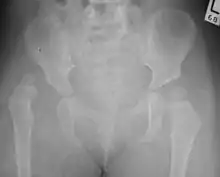

X-Ray Image showing hip dysplasia in a baby

Despite the widespread use of ultrasound, pelvis X-ray is still frequently used to diagnose or monitor hip dysplasia or for assessing other congenital conditions or bone tumors.[45]